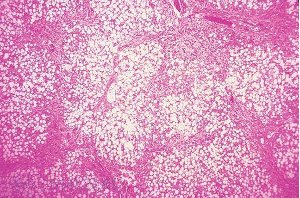

К основным гистологическим критериям цирроза печени относятся: окруженные соединительнотканными септами узлы регенерации паренхимы, не содержащие центральных вен; соединение септами сохранившихся центральных вен и портальных трактов. Нерегулярность архитектоники (наличие гепатоцитов различной величины, утолщение печеночных пластинок, неравномерное изменение просвета сосудов, избыток ветвей печеночной вены по отношению к числу портальных трактов).

Ткань печени в норме.

Микроскопическая картина цирроза печени, развившегося вследствие хронического гепатита С.

Цирроз печени вследствие аутоиммунного гепатита.

Для активного цирроза печени характерны: смазанность границ между септами и паренхимой, ступенчатые некрозы, лимфоидно-клеточная инфильтрация как фиброзной ткани, так и прилежащей паренхимы, набухание гепатоцитов, пролиферация желчных ходов на границе фиброзной ткани и паренхимы.

Гистологические признаки цирроза печени: фиброзные тяжи и микроузлы или псевдодоли. Псевдодоли представляют собой группы гепатоцитов, окруженные участками фиброза. Постепенно микроузлы превращаются в макроузлы.